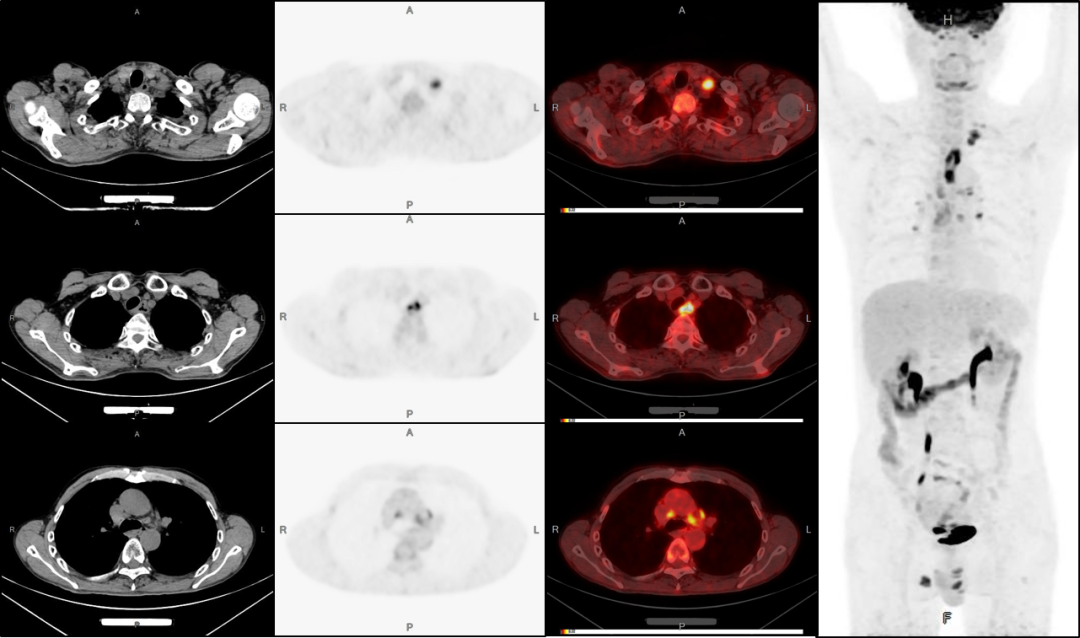

病例2:男性,51歲,反復咳嗽無痰半年余;發(fā)現(xiàn)左側(cè)鎖骨內(nèi)腫塊數(shù)月余。

2、肝臟轉(zhuǎn)移。

4、肝脾多發(fā)轉(zhuǎn)移灶可能。